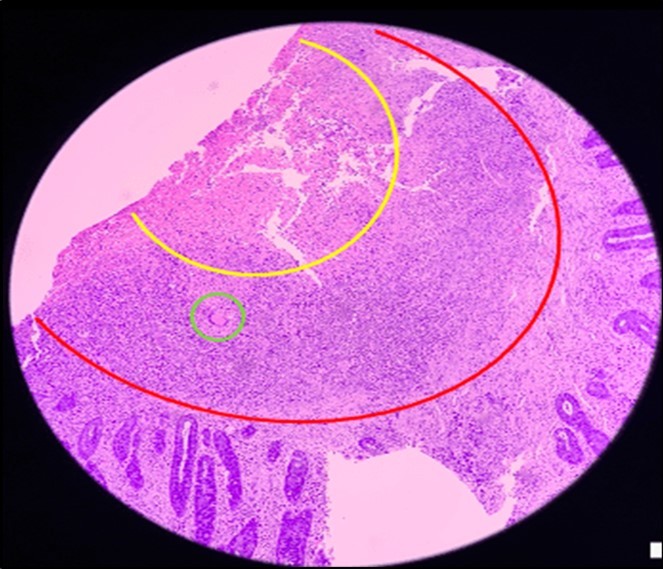

Figure 6.Pathologic slide in the low power field. The area inside the yellow circle is the area of central necrosis. The portion inside the red circle is the peripheral lymphocytic ring, and inside the green circle is the Langhan’s type multinucleated giant cells